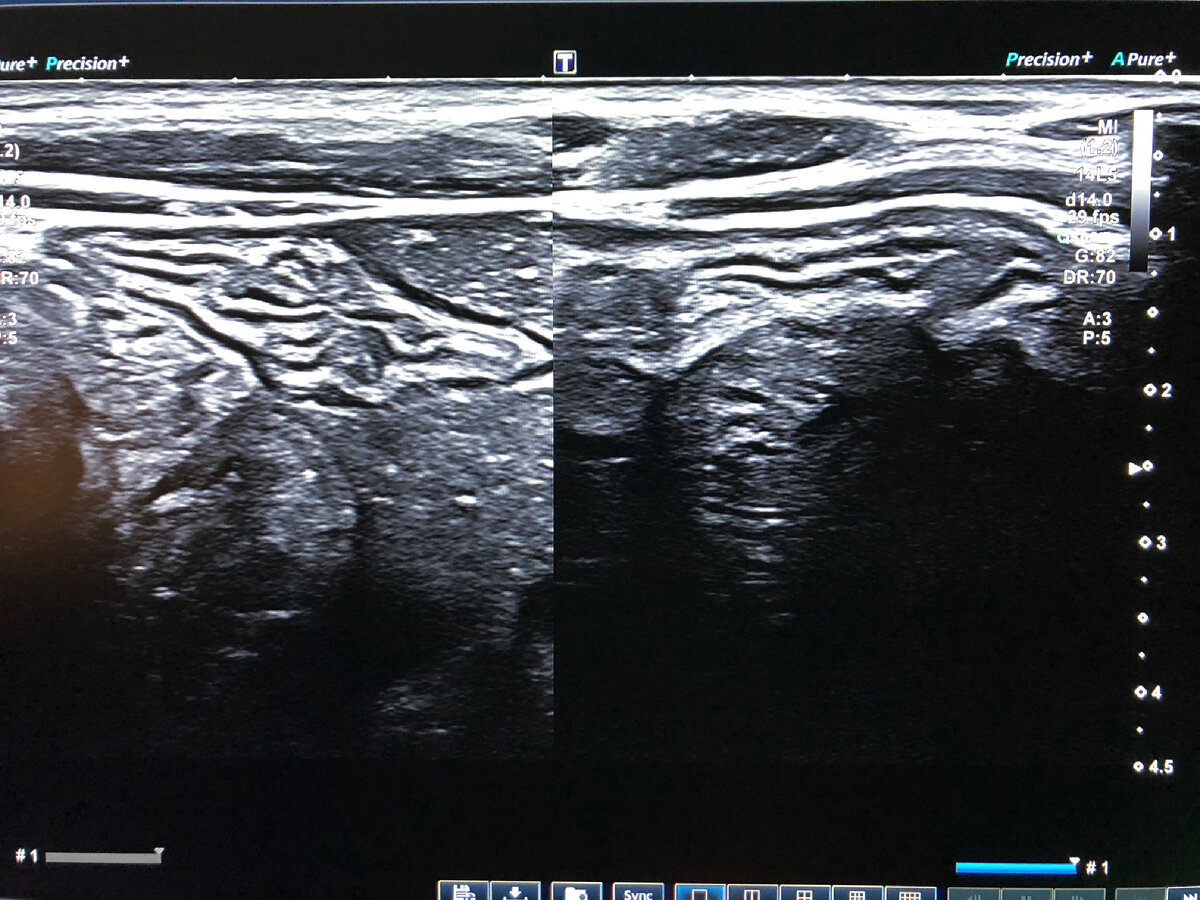

🔺Симптом поражённого полого органа (ППО) является наиболее частым описанием патологии желудка и кишечника в протоколах УЗИ органов брюшной полости несмотря на то, что он не имеет специфического характера и наблюдается при различных патологических состояниях.

🔺На экране прибора симптом ППО выглядит как образование округлой или овальной формы с относительно ровными контурами, периферическая часть которого представлена зоной пониженной эхогенности, а центральная часть – повышенной эхогенности.